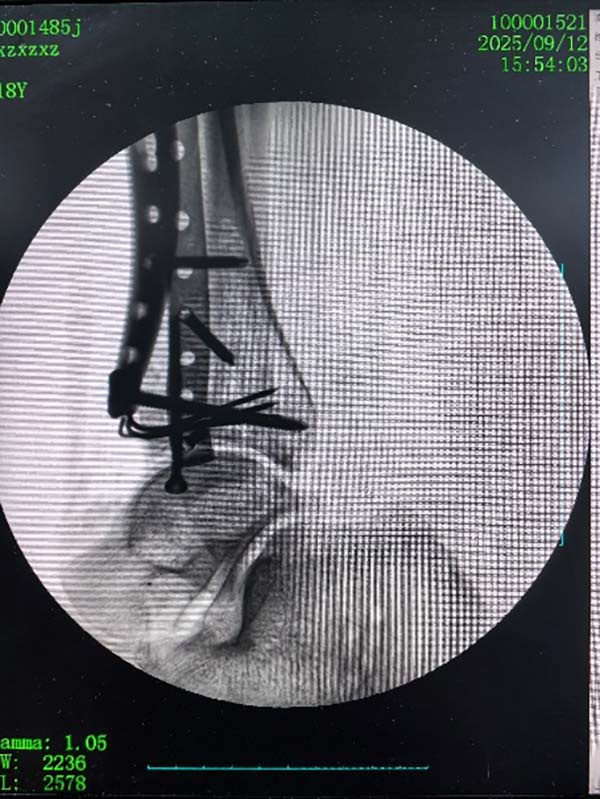

该款机器人适用于关节内骨折的撬拨复位及穿针定位,能够有效帮助医生对关节内复杂的骨折进行毫米级的定位、复位、固定操作。并能够结合前提课题完成的骨折AI识别规划软件,对骨折块进行撬拨复位。目前已在南阳市中医院开展临床研究三十余例。

两款联合使用复位复杂的Pilon骨折: